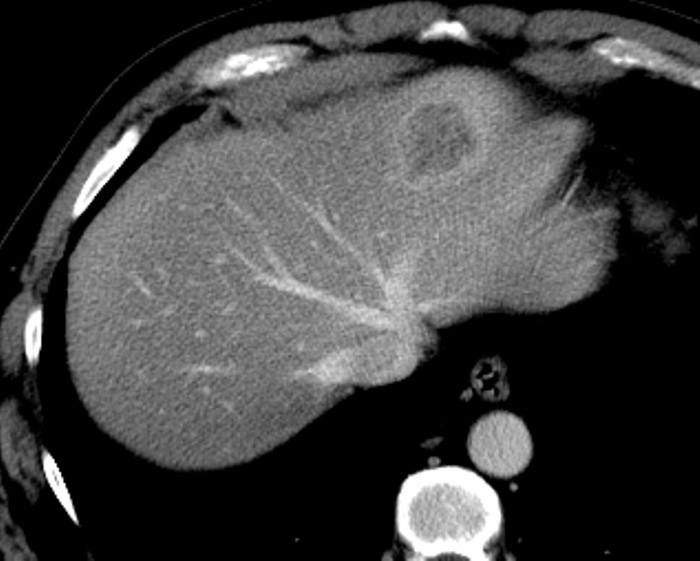

Ung thư đường mật

» Thông tin: Nam giới – 57 tuổi.

» Lâm sàng: Đau bụng.